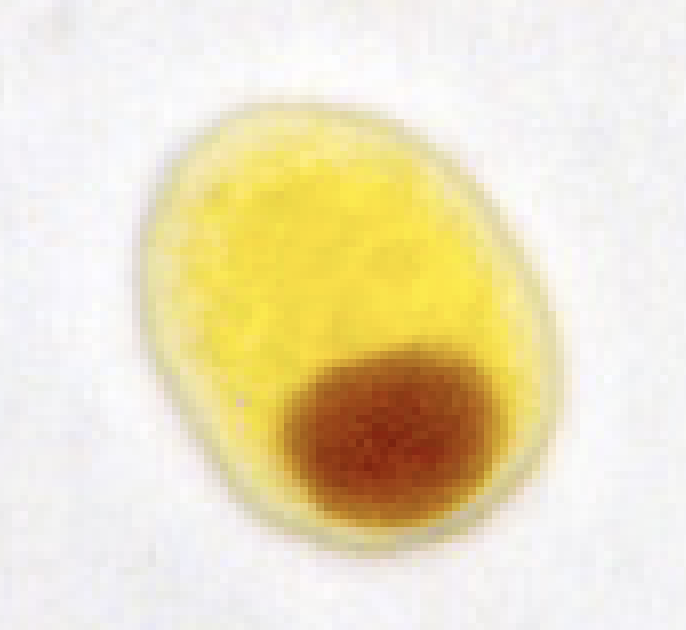

E. polecki cyst form may contain and inclsion body is it glycogen?

no

E. polecki cyst form